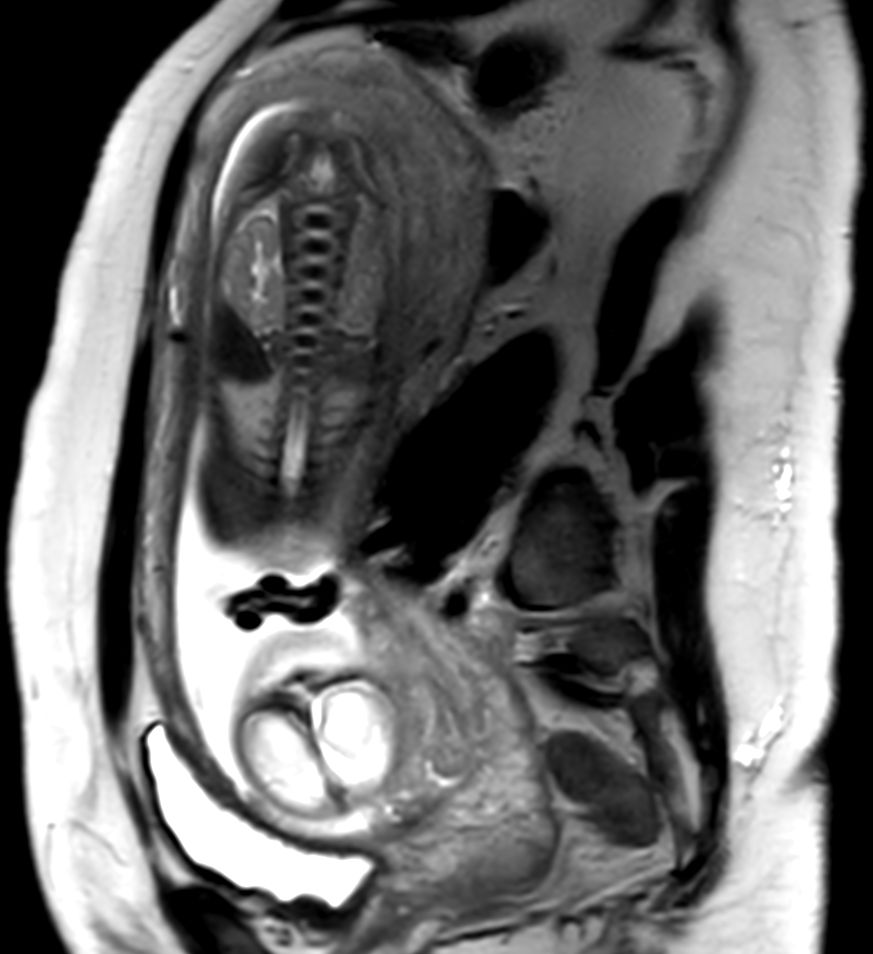

Sagittal T2w TSE single shot (Spine)Compressed SENSE